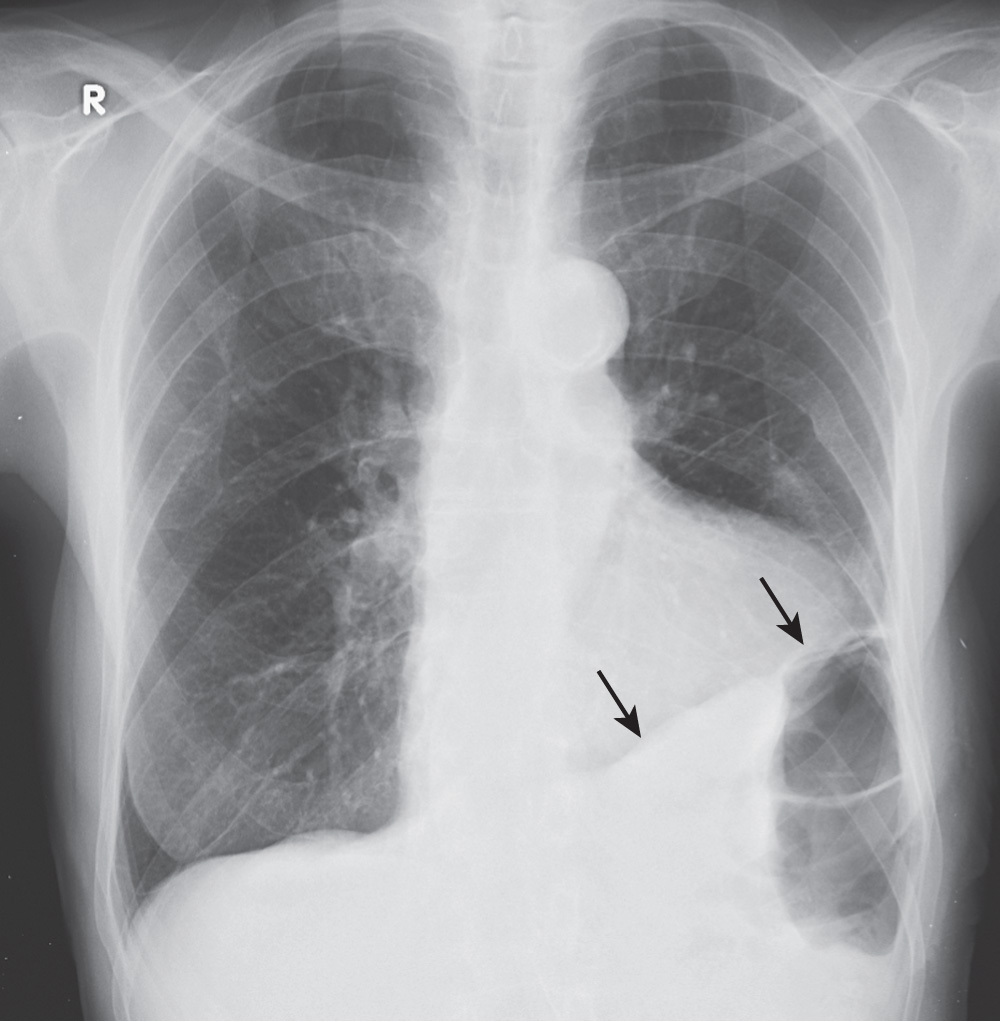

What is going on in this radiograph?

This radiograph shows a right pleural “pseudotumor”, aka fluid in the major fissure

A pleural “pseudotumor” is a loculated or localized collection of fluid in a major (oblique) fissure or right minor (horizontal) fissure and it can be mistaken for mass in the lung